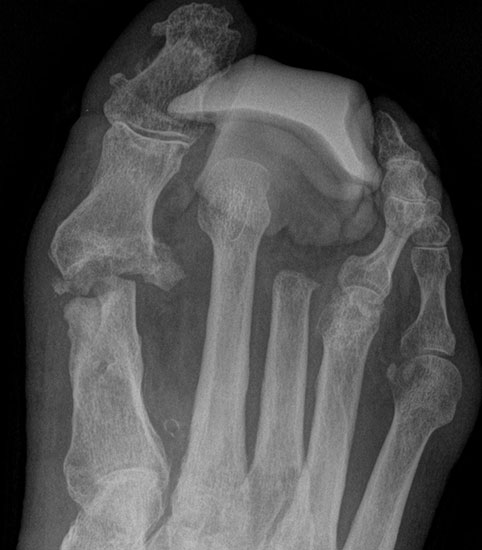

Es ist ungünstig, wenn wenige Kleinzehen lateral belassen werden. Das führt zum Kippen der Nachbarzehen oder zur Fehlstellung der verbliebenen Zehen (Abb. 18 - 20) und schließt eine optimale schuhtechnische Versorgung aus. Weitere Druckulzera sind zu erwarten. Die Großzehe kann als einzige Zehe belassen werden, wobei dann bisweilen die Arthrodese im Großzehengrundgelenk zur Stabilisierung ratsam ist (Abb. 21, 22).

• belassene störende Kleinzehen (Abb. 32).